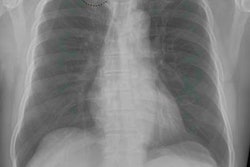

The potential for deep learning to objectively estimate bone mineral density on standard chest x-rays is the focus of this Monday presentation.Radiologists have long depended on dual-energy x-ray absorptiometry (DEXA) to evaluate conditions such the loss of bone mass (osteopenia) and the loss of bone density (osteoporosis). While osteopenia can be detected on x-ray, diagnoses are often subjective and come with high variability between readers.

This group of researchers, led by Dr. Peter Kamal from Johns Hopkins Hospital, sought to determine if artificial intelligence (AI) and deep convolutional neural networks (CNNs) could more reliably detect osteopenia and osteoporosis on chest radiographs.

The dataset included 875 postmenopausal women who had undergone DEXA scans and posteroanterior and lateral chest x-rays within three months of the DEXA scans. Training of the deep CNN was done with 70% of the x-ray images, while the remaining 30% were used for testing, ensuring no patient overlap.

A network architecture was created on a variety of standard deep CNNs and used to differentiate between normal bone mineral density, osteopenia, and osteoporosis, among other tasks. Its performance was measured using area under the curve (AUC) analysis.

Kamal and colleagues determined that the deep CNNs trained on posteroanterior radiographs outperformed the deep CNNs trained on lateral radiographs. The AI algorithms also detected osteopenia or osteoporosis with an AUC of 0.78 from posteroanterior radiographs and an AUC of 0.73 on lateral radiographs. When the AI model was asked to distinguish between osteoporotic and normal radiographs, AUC reached 0.87.

Deep CNNs can provide "an objective method for the prediction of osteopenia and osteoporosis on chest radiographs, which suggests potential use for opportunistic screening of these conditions," the researchers concluded.